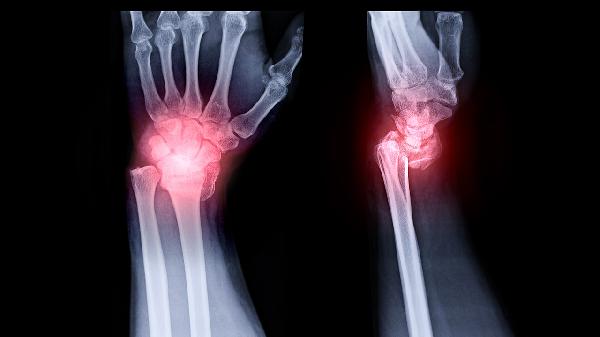

高分辨率CT能清晰显示骨瘤的钙化程度与周围骨质关系,MRI则有助于评估肿瘤对筛窦黏膜及眼眶、颅底的潜在影响。影像学动态对比是判断肿瘤生物学行为的关键依据。